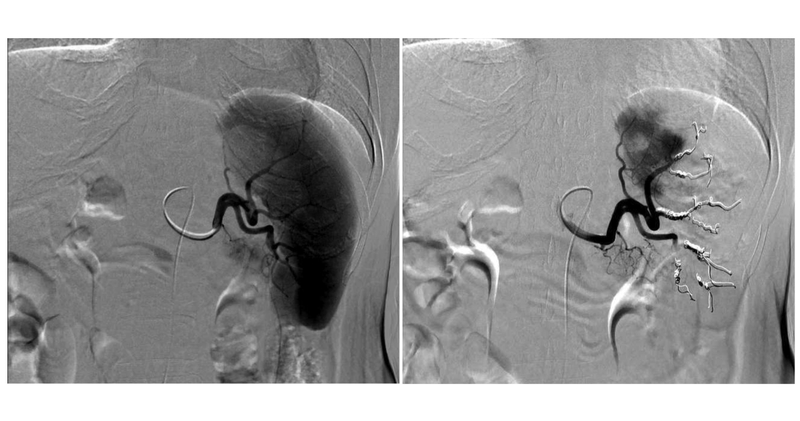

静脈瘤に対してはおもに内視鏡治療を行いますが、胃静脈瘤に対してはバルーン閉塞下逆行性経静脈的塞栓術(B-RTO)というカテーテル治療が有効な症例もあります。

また、脾腫・脾機能亢進による血小板減少に対する治療法として、部分的脾動脈塞栓術(PSE=カテーテル治療)や脾臓摘出術(外科手術)があります。